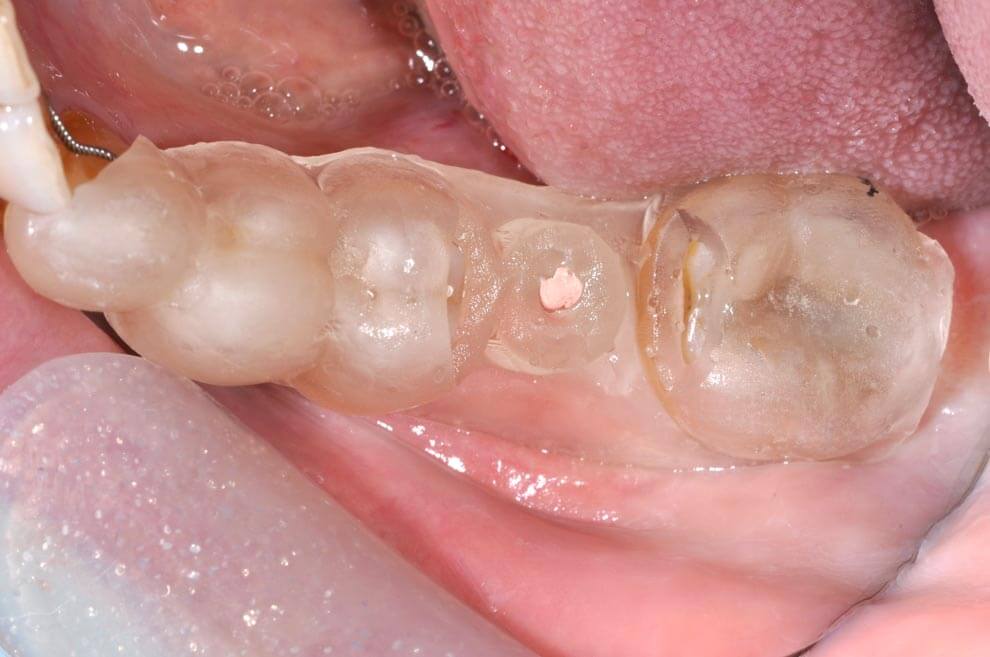

臨時假牙/牙齦塑形器

常常覺得植牙完後會卡食物嗎? 現在用牙齦塑形器就可以避免了。

在安裝正式植牙假牙前,會先按照電腦規劃的結果設計,製作臨時假牙/牙齦塑形器,用來塑形牙肉使其恢復至正常的牙縫型態,避免日後發生卡牙縫的問題。